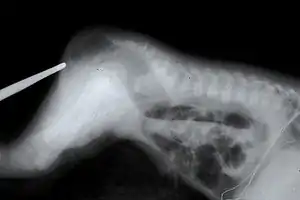

| An example of the defect after which CES is named. | |

The term "cat eye" syndrome was coined because of the particular appearance of the vertical colobomas in the eyes of some patients. However, over half of the CES patients in the literature do not present with this trait.[4]